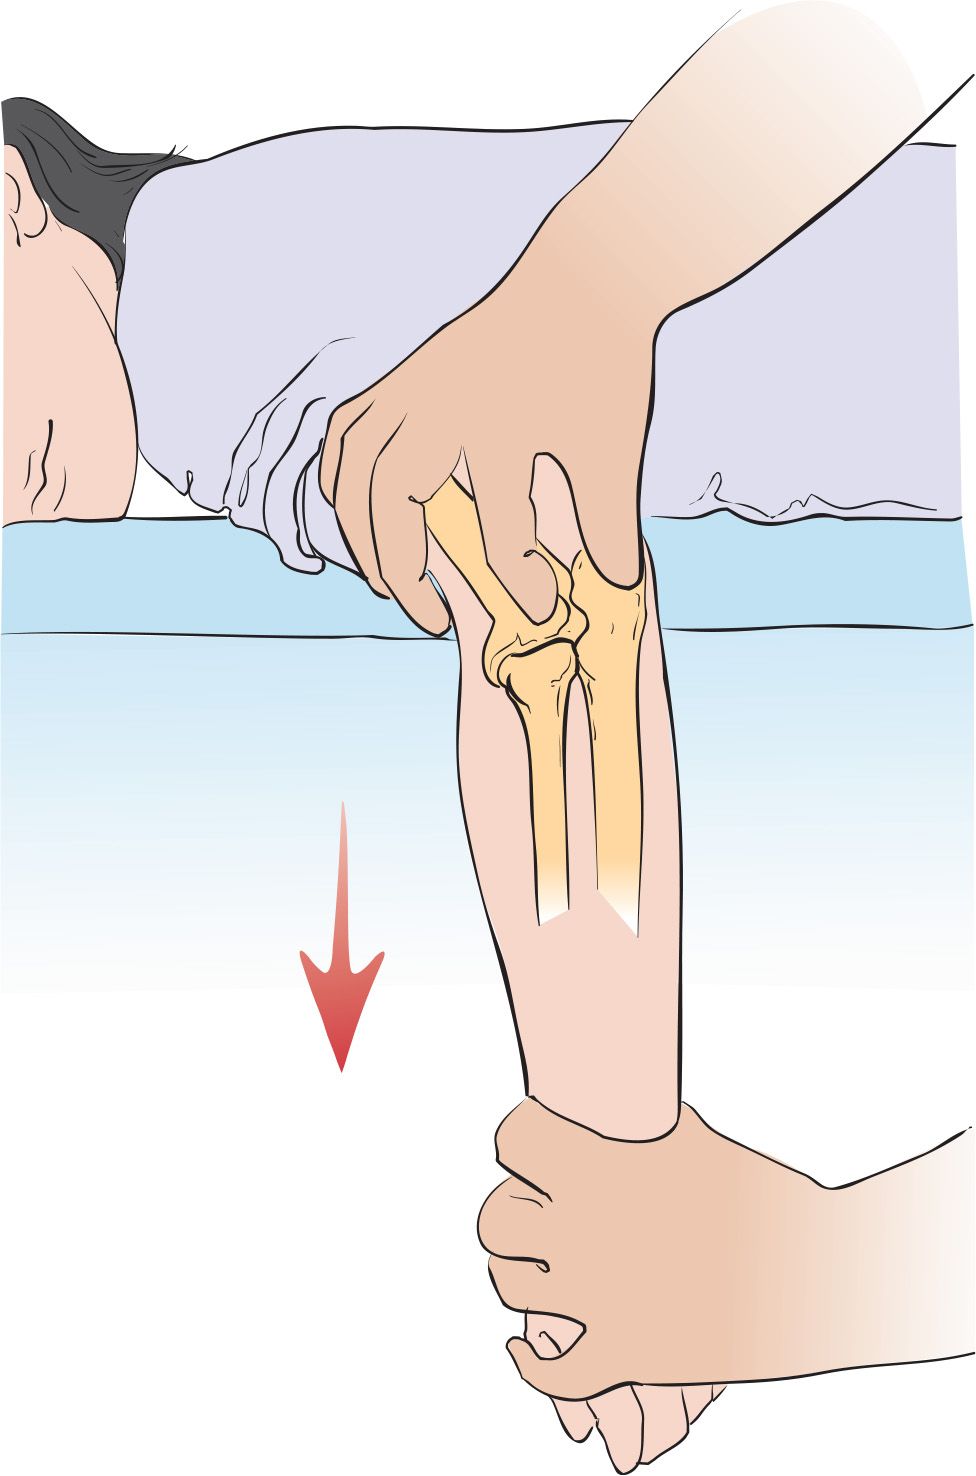

If this is performed externally, that is, without opening the arm, it is known as closed.

Caution can help reduce your risk of a dislocated elbow. The act of restoring alignment to the elbow is called a reduction maneuver. Types of reduction of elbow dislocation first aid immediately after the injury you should put.

Listen for a click or a palpable pop at the radial head, which. A gentle pull and push and the elbow could be back in place. Often, in addition to a dislocation, there is a fracture with displacement of bone fragments, etc.

In this video we treat a patient with a posterior elbow dislocation. It is done gently and slowly. Ad browse & discover thousands of brands.

Sedation and muscle relaxers may be necessary to correct your elbow dislocation. This clip describes why elbow dislocation is hard to achieve in dogs, but when it occurs, how it is reduced. What are the risk factors for.